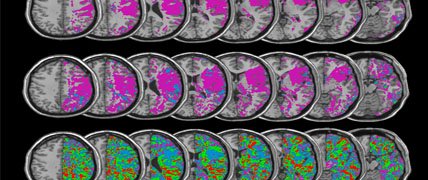

Weltschlaganfalltag 29.10.2025: Neue Forschungsgruppe am HIH

Jedes Jahr erleiden rund 270.000 Menschen in Deutschland einen Schlaganfall. Liegt ein Verdacht auf einen Schlaganfall vor, zählt jede Minute. Anlässlich des Weltschlaganfalltages am 29. Oktober begrüßen wir recht herzlich PD Dr. Annerose Mengel am HIH. Sie leitet ab sofort ihre eigene Forschungsgruppe "Schlaganfallerholung und Outcome“ in der Abteilung „Neurologie mit Schwerpunkt neurovaskuläre Erkrankungen“ von Prof. Ulf Ziemann.